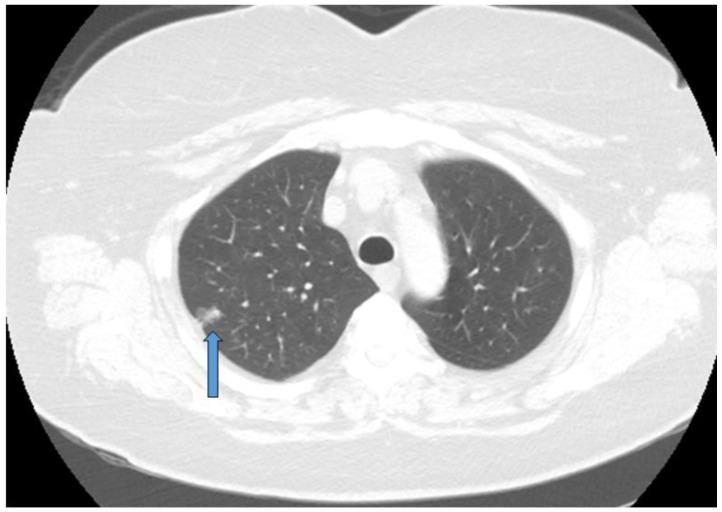

亚肺叶切除术在非小细胞肺癌外科治疗中的作用。

The Role of Sublobar Resection for the Surgical Treatment of Non-Small Cell Lung Cancer.

Lung cancer is the most common cancer killer in the world. The standard of care for surgical treatment of non-small cell lung cancer has been lobectomy. Recent studies have identified that sublobar resection has non-inferior survival rates compared to lobectomy, however. Sublobar resection may increase the number of patients who can tolerate surgery and reduce postoperative pulmonary decline. Sublobar resection appears to have equivalent results to surgery in patients with small, peripheral tumors and no lymph node disease. As the utilization of segmentectomy increases, there may be some centers that perform this operation more than other centers. Care must be taken to ensure that all patients have access to this modality. Future investigations should focus on examining the outcomes from segmentectomy as it is applied more widely. When employed on a broad scale, morbidity and survival rates should be monitored. As segmentectomy is performed more frequently, patients may experience improved postoperative quality of life while maintaining the same oncologic benefit.

摘要